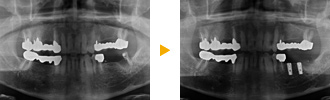

兵庫県宝塚市60代男性:下顎の左右に合計3本のインプラント埋入

兵庫県宝塚市60代男性の症例です。

歯周病で下の奥歯を失われ、入れ歯にしておられましたが、歯周病治療で歯ぐきの状態が改善したため3本のインプラントで治療しました。

治療方法

右下奥歯に2本、左下奥歯に1本インプラントを埋入しました。